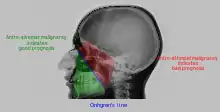

المَنْظَرِ بحسب وَتَر (المعروفة أيضًا باسم صورة قَذَالِيٌّ ذَقْني) هي صورة شعاعية، حيث يتم إسقاط الأشعة السينية بزاوية 45 درجة على خط صماخ الحجاجي (orbitomeatal line).[48] وتمر الأشعة من خلف الرأس وتكون متعامدة على صفيحة التصوير الإشعاعي. وتستخدم تلك الطريقة للحصول على صورة أفضل للجيب الفكي العلوي.

الأشكال المصورة

- جيب فكي علوي

- الجيب الجبهي (منظر مائل)

- جيب غربالي

- الجيب الوتدي (عبر فم مفتوح)

- نُتوء سني الشكل (إذا كان أسفل الذقن، فهو يؤكد الامتداد المناسب للرأس)

المشاهدات الممكنة

| التهاب الجيب الفكي العلوي | ![]() تمييز الأمراض في الجيب الفكي العلوي

| الخباثة |

![]() خط Onhgren